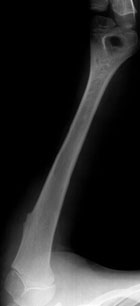

Manuel Z., anni 9, è stato seguito dal suo pediatra per la presenza di una tumefazione nella regione anteriore della spalla sinistra. All’età di 3 anni, infatti, il bambino era stato mandato all’osservazione dello specialista ortopedico per la comparsa della suddetta tumefazione. Essa appariva di consistenza dura, della dimensione di 2 centimetri per 1 e mezzo circa, libera sui piani superficiali ma adesa su quelli profondi; il termotatto non era aumentato, la cute soprastante indenne, i linfonodi nel cavo ascellare non interessati. Il sospetto era stato subito che la tumefazione fosse a provenienza dall’osso ed era stata suggerita l’esecuzione di un radiogramma dell’omero e non di un’ecografia delle parti molli, come poteva sembrare più logco aduna superficiale analisi. Il radiogramma aveva evidenziato la presenza di una esostosi peduncolata del terzo prossimale dell’omero. Poiché tale esostosi era sempre stata del tutto asintomatica, non si poneva l’indicazione chirurgica. Da un accurato esame clinico di tutto il corpo tale esostosi risultava isolata e non facente parte di una malattia esostosante. Alla madre venne consigliato, quindi, di portare il bambino a controllo una volta all’anno per una valutazione clinica dell’estensione delle dimensioni dell’esostosi e dell’eventuale comparsa di sintomatologia algica. Nei controlli periodici che si susseguirono negli anni l’esostosi risultò invariata. All’ultimo controllo, risalente a un mese fa, essa risultava lievemente ingrandita, diventando visibile ad occhio nudo, ed iniziava a dare al bambino la sensazione di averla: venne posta così l’indicazione chirurgica. Si scelse di asportarla durante le vacanze scolastiche, evitando al bambino di perdere due giorni di scuola. Due settimane prima della data prevista dell’intervento, in seguito a un trauma ricevuto nel corso di una partita di pallacanestro a scuola, il bambino accusò un fortissimo dolore al braccio sinistro.

Portato al Pronto Soccorso, eseguiva un radiogramma del braccio che evidenziava la rottura dell’esostosi a livello del suo peduncolo d’impianto. L’esostosi fu asportata il giorno seguente.